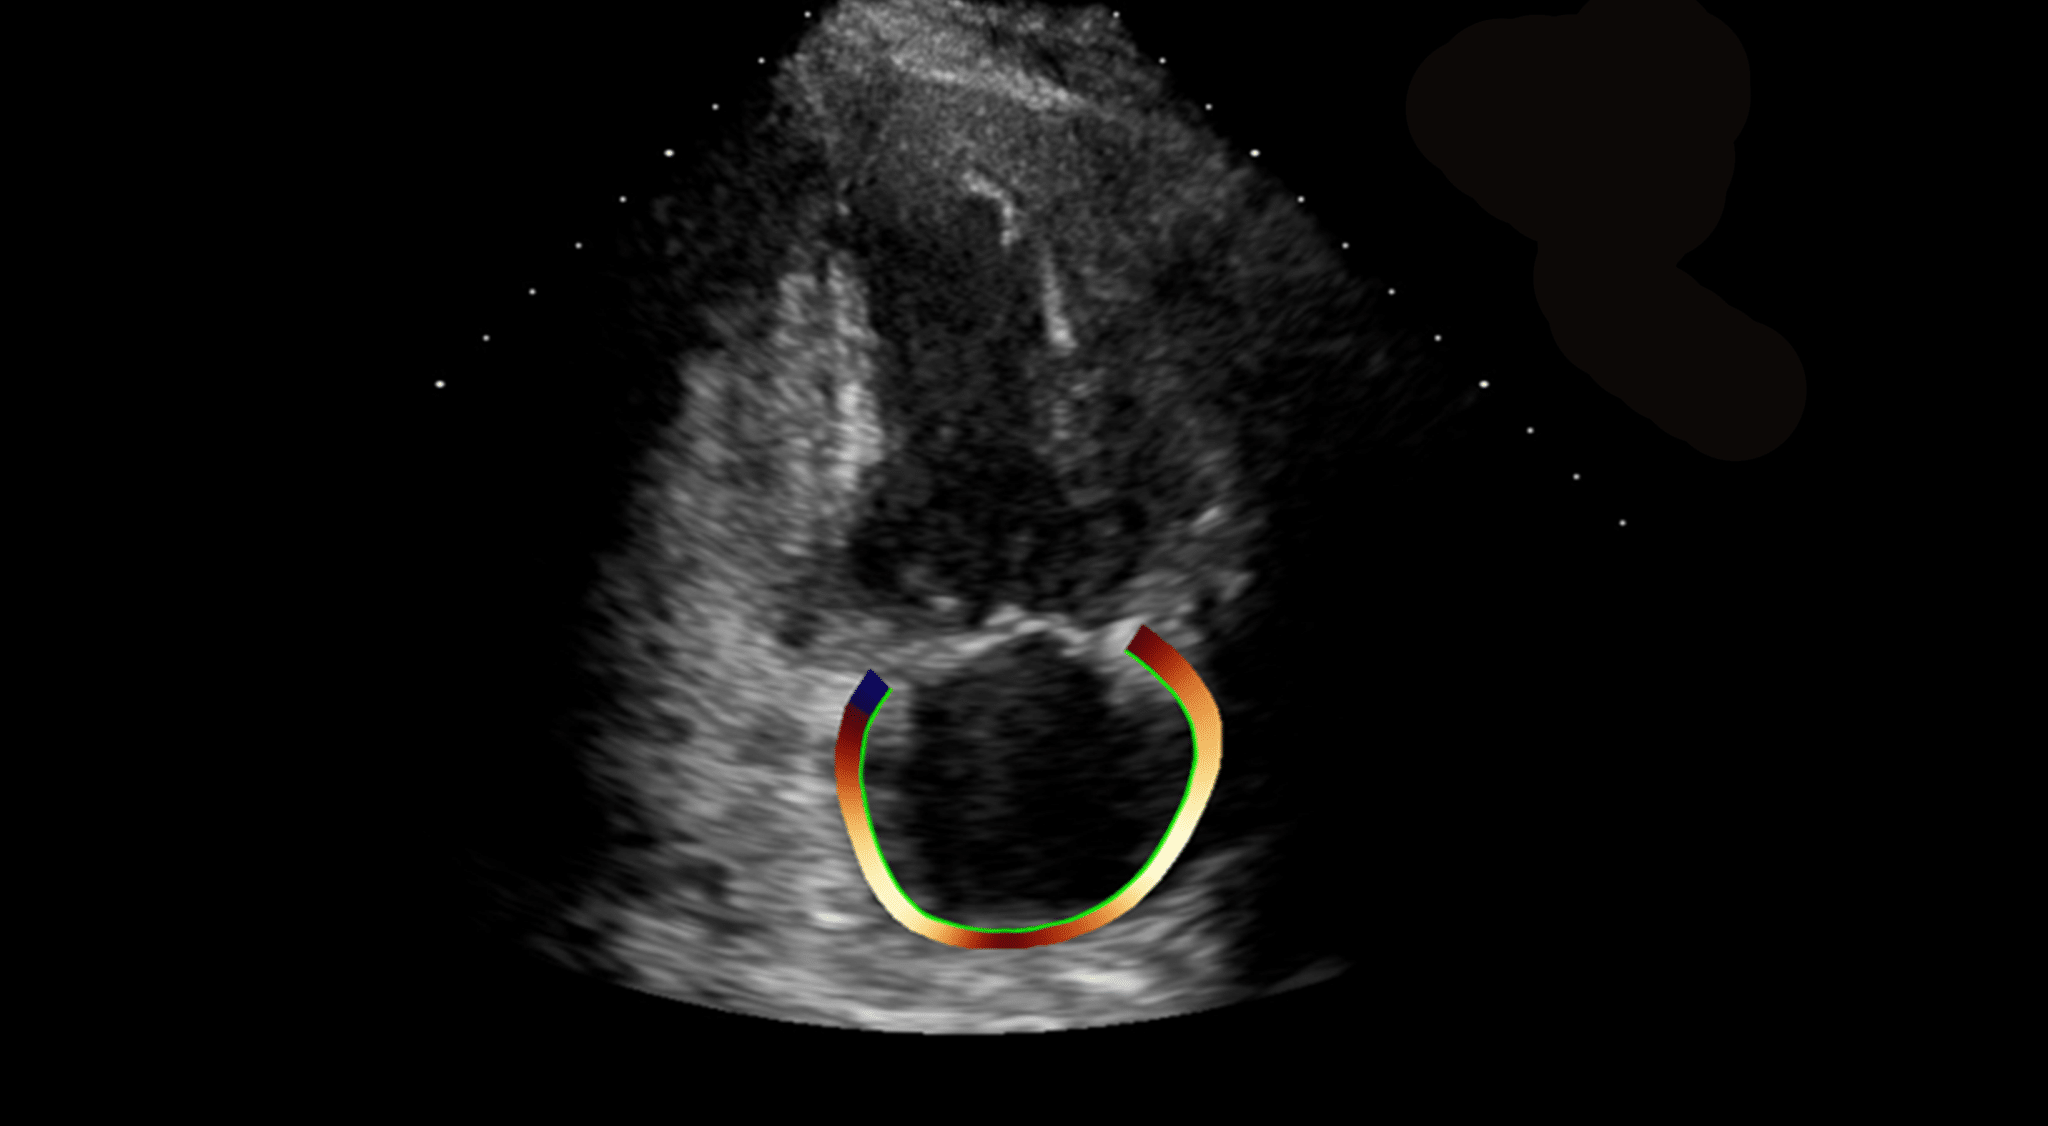

- Allows the quantitative evaluation of the Left Ventricle, Right Ventricle and the Left Atrium OEM solution. See the applications below for further details